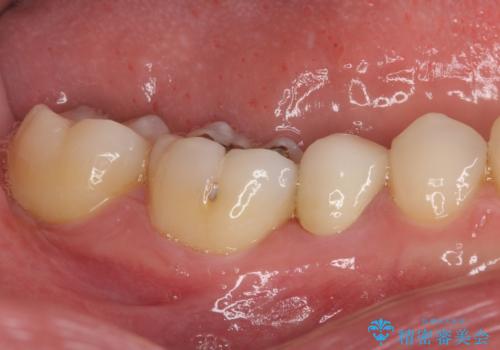

- 上下前歯のデコボコと銀歯のブリッジを気にして来院された患者様です。

装着されているブリッジを切断して矯正治療を行うことや、手間をかけずに早めに治療を終えたいとのことで、目立たないワイヤー装置による矯正治療を行うこととしました。

矯正治療後には切断したブリッジをオールセラミックブリッジに置き換えることとしました。